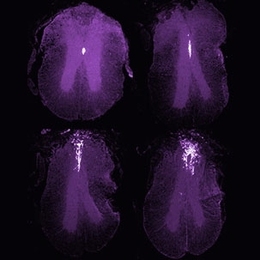

Study points to dietary cocktail for Alzheimer's Supplement improves memory, learning in gerbils July 8, 2008 Read full story →